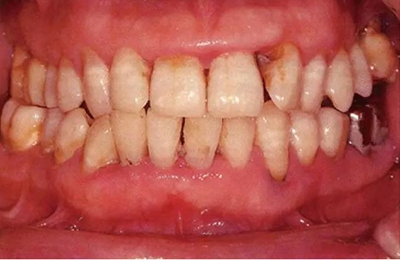

患有牙周病的牙周組織的臨床照片

55歲牙周炎男性的臨床照片

55歲男性抽煙患者(1天20支、抽煙35年)。菌斑控制得不好。通過(guò)牙周探診,全頜有4~9mm的牙周袋,有1~3度的根分叉部病變。通過(guò)X光片觀察,上頜前牙中度牙槽骨吸收,其他地方有中度牙槽骨吸收。受吸煙影響,牙齦纖維性肥厚,呈紅黑色。牙齦幾乎沒(méi)有浮腫和發(fā)紅,所以這個(gè)病例是從外觀上無(wú)法預(yù)測(cè)病癥嚴(yán)重程度的病例。